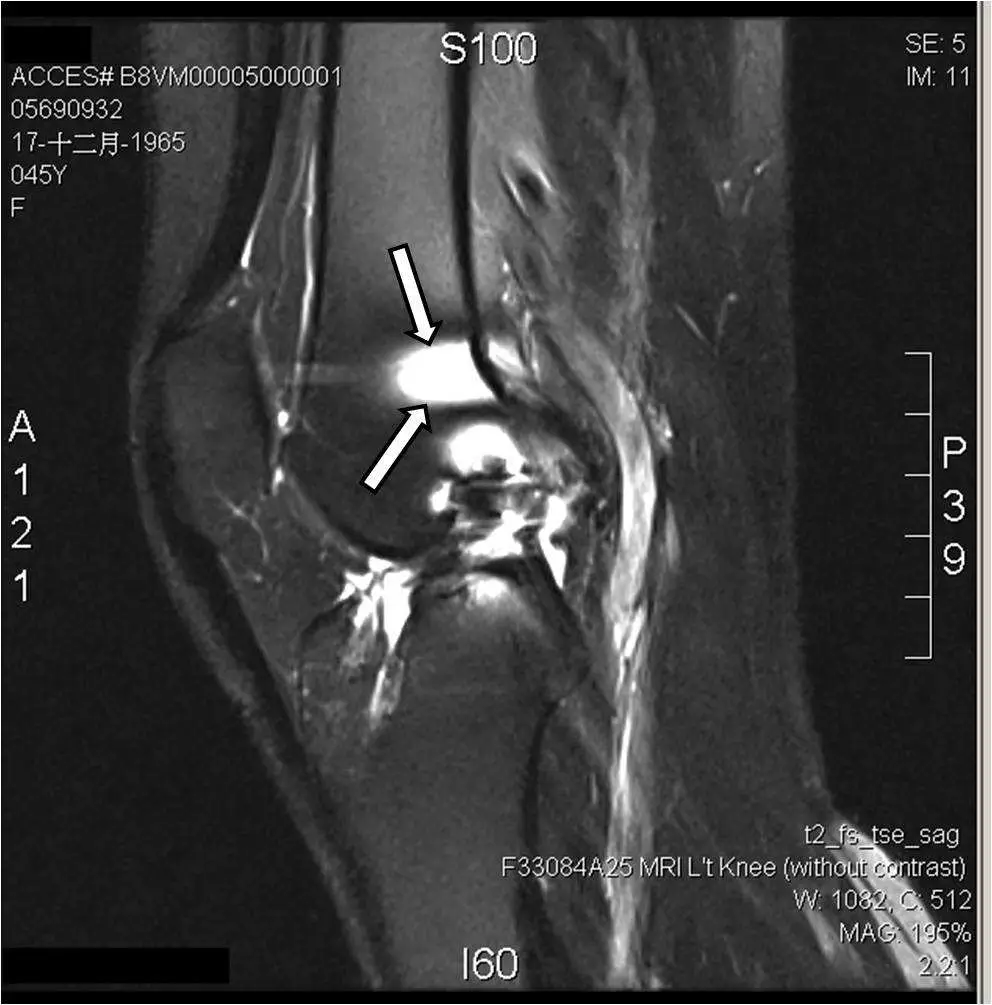

下圖為膝關節矢狀面 T2-weighted MRI ,箭號所指處為下列何種假影?

本題考核膝關節 MRI T2 加權影像上假影的辨識,重點為「磁化率假影(magnetic susceptibility artifact)」的成因、影像特徵及鑑別。影像顯示膝關節矢狀面 T2-FSE 脂肪抑制影像,箭號指向關節面附近出現局部訊號異常的區域,需與截斷假影、運動假影及混疊假影鑑別。

影像為左膝矢狀面 T2-weighted fast spin-echo(FSE)脂肪抑制 MRI(序列顯示為 t2_fs_tse_sag),45 歲女性。兩個白色箭號指向**脛骨平台(tibial plateau)與股骨髁交界區(關節間隙附近)**的一個局部區域,該處呈現:

- 局部極亮的高訊號(bright focus)

- 鄰近區域有訊號空洞(signal void / dark area)

- 整體形態不符合正常解剖結構(非韌帶、非積液)

- 無沿相位編碼方向的條紋或鬼影

此訊號特徵(局部亮訊號 + 鄰近暗訊號空洞,邊界不規則)為典型的磁化率假影(magnetic susceptibility artifact)表現:局部磁場失真造成訊號堆積(pile-up)→ 異常高訊號,同時鄰近區域訊號移走 → 低訊號空洞。

在膝關節 T2-FSE 影像上,此類假影常見原因包括:含鐵血黃素(hemosiderin)沉積(來自先前出血)、